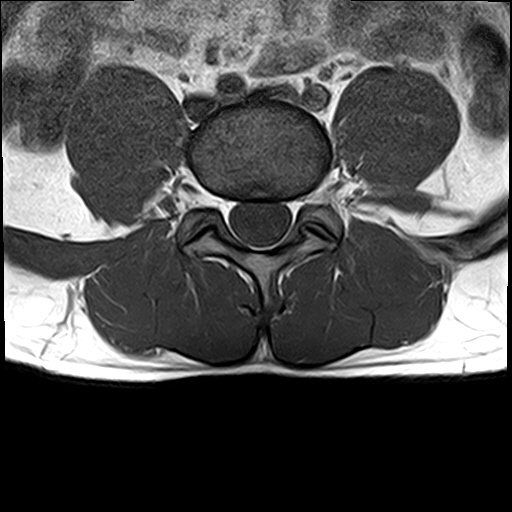

선생님 요추 Mri 판독부탁드립니다 ㅠㅠ

예전 진료에서 척추전방전위증과 그로인한 퇴행성 디스크 그리고 팽윤이 있다고 들었습니다.

현재 제가 디스크가 터진곳이 있을까요?

집근처 병원을 세곳을다니는중인데 어떤곳은 디스크는 멀쩡하다 퇴행성만있을뿐.

어떤곳은 디스크가 터졌다고 하는게 어떤곳이 맞는건가요?

혹시 디스크가 터진게 없다면 통증이 생기는이유는 단순히 척추전방증으로인한 퇴행성디스크와 팽윤 때문인건가요?

디스크가 명확하게 튀어나와 신경뿌리를 압박하는 병변은 보이지 않는 MRI로 생각됩니다.